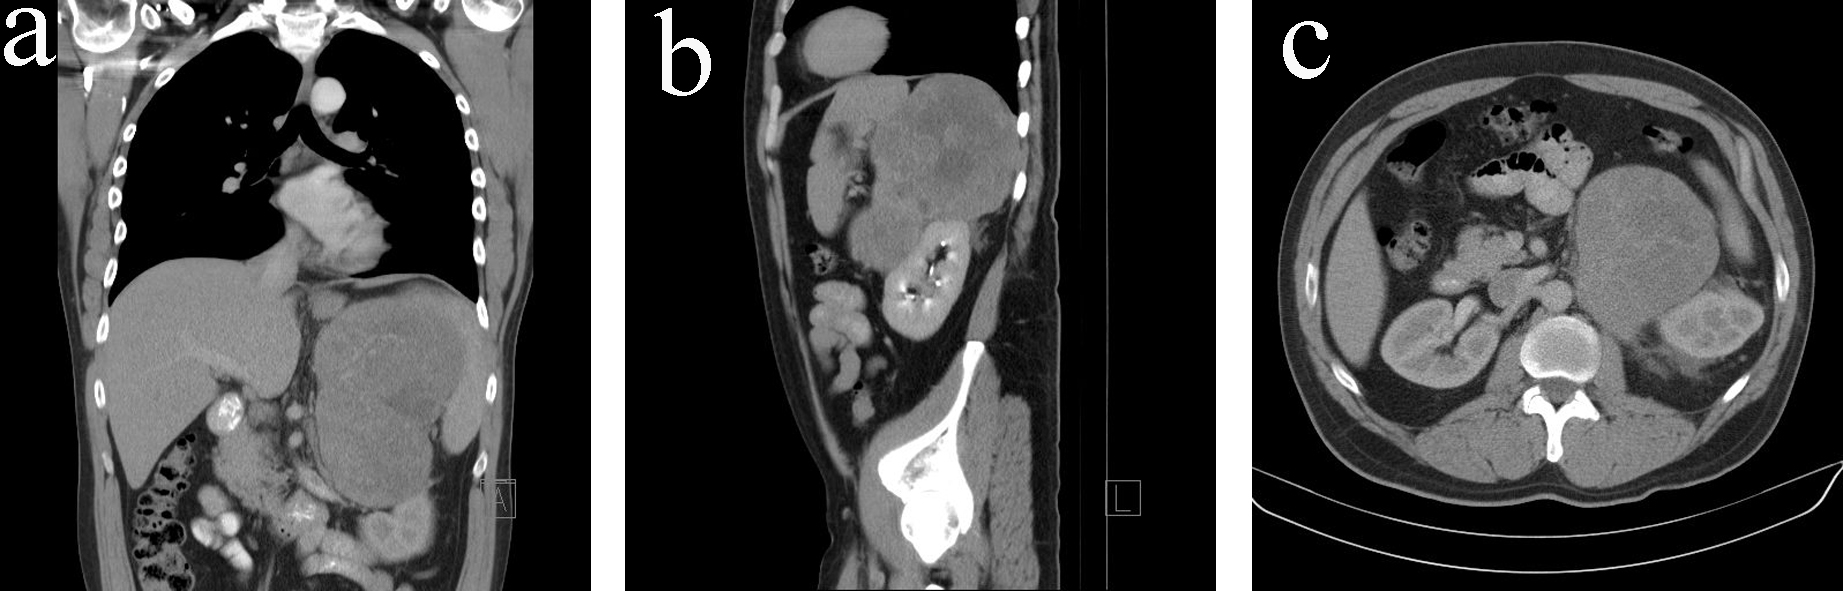

A 38-year-old man with no significant past medical history presented with left-sided chest pain, dyspnoea on exertion and left flank pain in April 2011. He was found to have left lower lobe segmental pulmonary embolus on a VQ scan, together with an incidental finding of a large soft tissue mass (15.5 × 12.0 × 16.7 cm) with no arterial phase enhancement, immediately superior to the left kidney in the CT scan. No local or distant metastases were noted in the staging CT scan (Fig. 1).

![]() Click for large image | Figure 1. (a) CT scan (coronal view) on initial diagnosis. (b) CT scan (sagittal view) on initial diagnosis. (c) CT scan (transverse view) on initial diagnosis. |